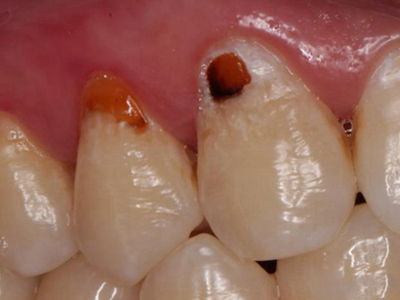

酸蚀症牙齿缺损不平整图

酸蚀症患者的牙齿会发生缺损,轻度时仅表现为牙齿尖端凹凸不平,有少量骨质缺失,缺损处有黄褐色至红褐色斑点,该病可能是长期接触外源性酸性物质而致病。